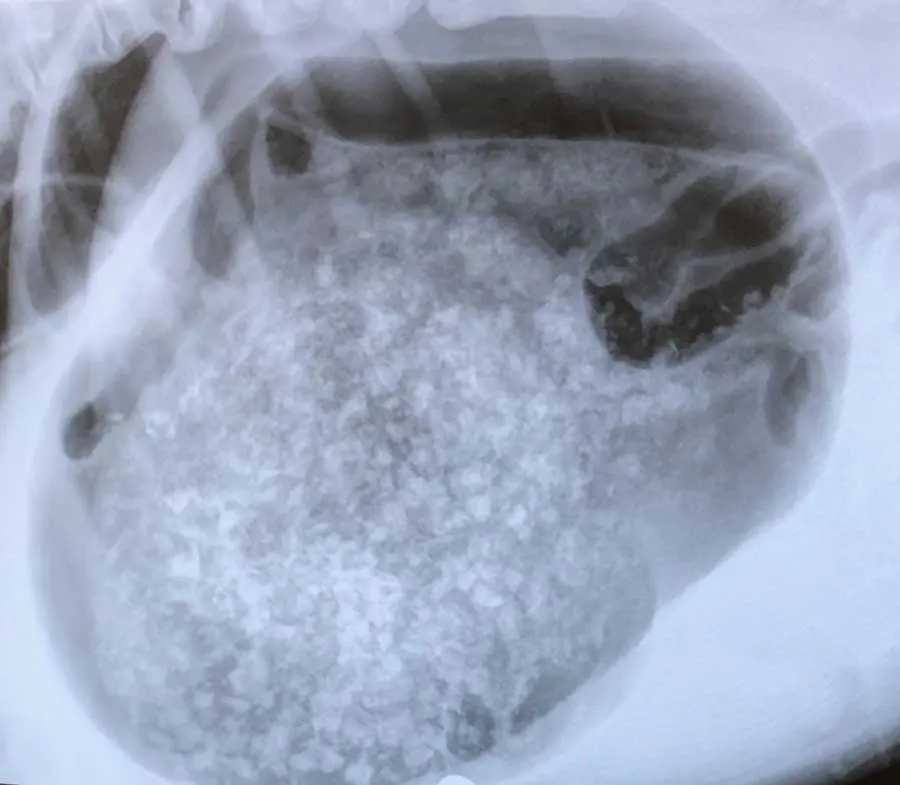

Radiographs can identify injuries or disease processes within the body by visualising bones, organs and other soft tissue structures – anything from fractures and osteosarcomas to bladder stones, foreign bodies and gastric dilation volvulus.

In more recent years, dental radiography has become a more common sight in first opinion practices, with the aim to identify tooth structures below the gingival margin, within the bone – pathology that remains undetected otherwise (Milella, 2022) – with recent studies showing that 27.8% of findings in dogs and 41.7% of findings in cats would be missed (Van Velzen, 2024).